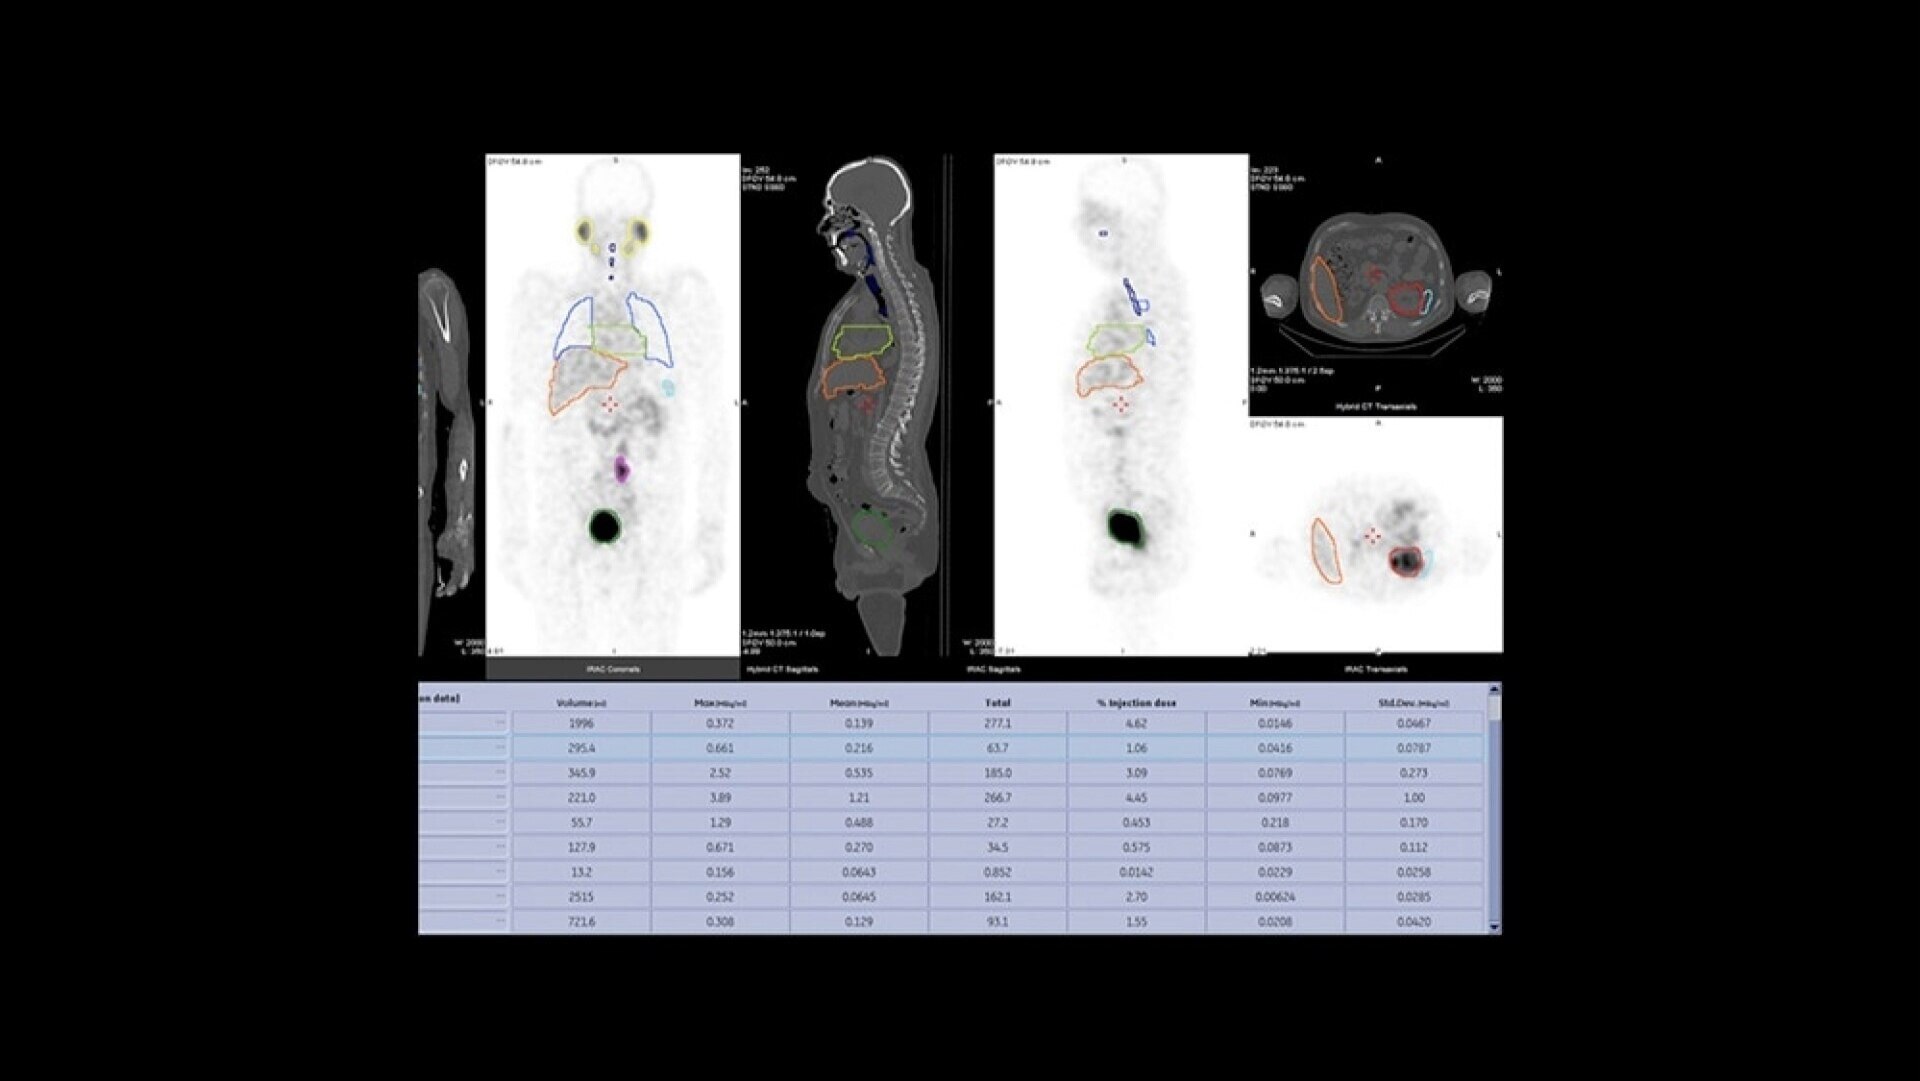

Built for Quantitation

Quantitative SPECT/CT for every patient, every day

NM/CT 870 CZT is a SPECT/CT built for consistent, reproducible quantitation. Improvements to detector performance enable exceptional spatial and energy resolution. It also leverages CT-based attenuation and scatter correction along with Evolution3 image reconstruction. In addition, ever-increasing computational power enables precise camera calibration for less variation between exams.

Once your quantitative studies are acquired, SmartConsole - together with Xeleris - makes it easier to access them. Your quantitative SPECT/CT studies are automatically transferred directly to the PACS or other pre-defined DICOM destinations. An additional dataset in PET DICOM format allows you to review and evaluate images on the same devices you use to view your PET/CT studies, as adjacent information to the original SPECT/CT images.

One home for all your molecular images

SmartConsole makes advanced procedures more accessible by transferring exams directly to the PACS or other pre-defined DICOM destinations with no operator intervention, even if SPECT/CT fusion is not supported, by exporting the studies in DICOM PET format. You can generate and send an additional dataset in PET DICOM format to enable quantitative SPECT results and SPECT SUV (Standard Uptake Value) on any PET DICOM compliant workstation or PACS. Referring physicians can review and evaluate your SPECT/CT exams with the same quality of information they have come to expect from your PET/CT, as adjunct information to the original SPECT/CT images.